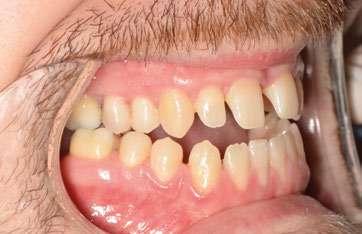

2. Análisis intraoral (Ilustración 2 y 3):

 Clase III molar y canina de Angle bilateral.

 Mordida abierta anterior > 3 mm.

 Compresión maxilar junto con mordida cruzada posterior bilateral.

 Línea media inferior desviada 2 mm hacia la derecha.

Ilustración 2. Fotografías intraorales iniciales de estudio.

Ilustración 3. Modelos iniciales de estudio.